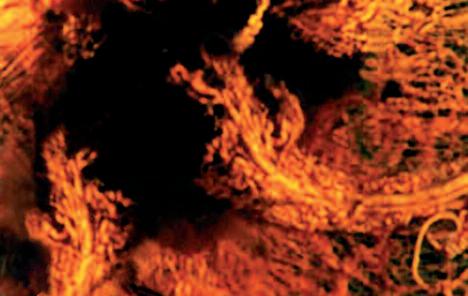

La pagina a fianco mostra l'immagine di una cellula tumorale reale, visualizzata al microscopio elettronico, che ingrandisce questa cellula 6500 volte rispetto alle sue normali dimensioni. Questo tipo di cellula prende il nome di carcinoma, cioè derivante da cellule epiteliali, il tipo di cellule che rivestono sia le superfici interne (polmoni, intestini) che esterne (pelle) del corpo.

Grazie a questo ingrandimento si possono identificare chiaramente alcune delle caratteristiche di tutte le cellule tumorali: a) l'enorme nucleo cellulare dalla forma insolita che spiega la loro grande capacità di riprodursi e b) la struttura non uniforme, complessa della superficie cellulare, che riflette una forte attività di secrezione di sostanze prodotte dalle cellule tumorali.

Una delle più importanti molecole secrete dalle cellule tumorali in grandi quantità sono gli enzimi a ‘forbice’ che digeriscono il collagene. Sono aggiunti graficamente a questa immagine, sotto forma di strutture simili ad un ‘pacman’ rosso.

La foto nella pagina a fianco mostra una cellula cancerogena ad un microscopio.

Il corpo di questa cellula tumorale in migrazione si espande nella direzione del suo movimento all’interno del tessuto. Può formare una struttura ‘tentacolare’ che trascina la cellula tumorale lungo la superficie, in questo caso, di un vaso sanguigno.

Gli enzimi che digeriscono il collagene sono aggiunti per illustrare il processo mediante il quale qualsiasi ostacolo sul cammino di questa cellula tumorale viene superato.